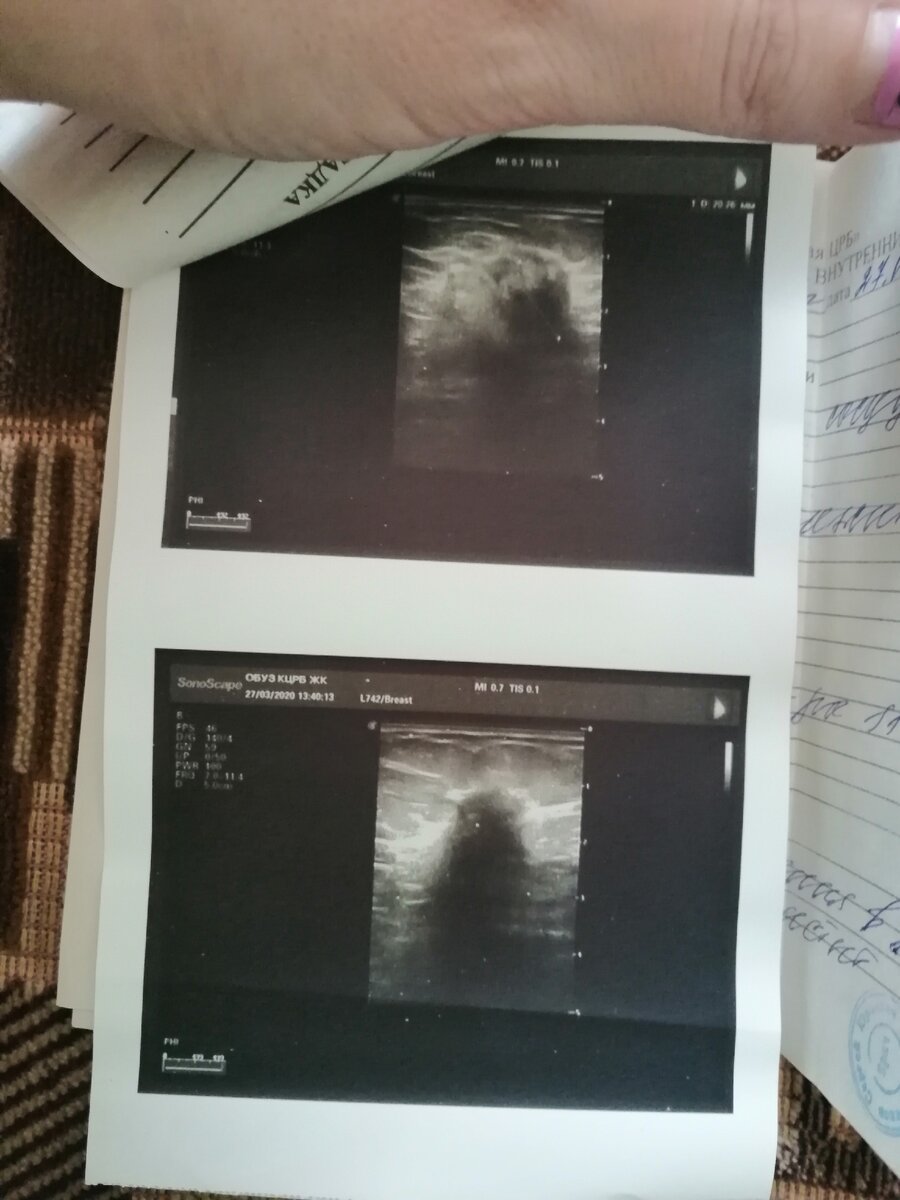

Онкология это приговор или другая жизнь?